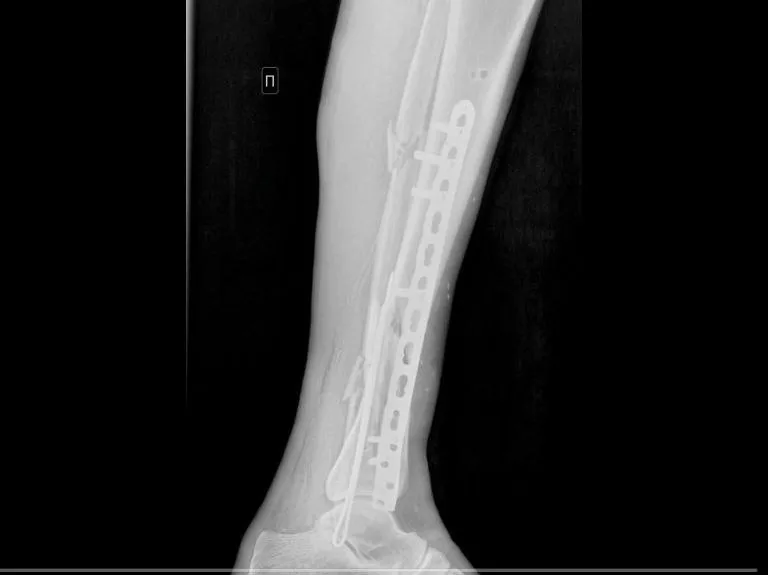

По неосторожности нога пострадавшего попала во вращающий механизм, что привело к тяжелым повреждениям: открытый оскольчатый перелом правой голени, рваная рана бедра и большая лоскутная рана на левой голени. Когда мужчину доставили в больницу, его нога была холодной и посиневшей из-за отсутствия кровотока.

На следующем этапе операции врачи использовали титановую пластину для остеосинтеза, что позволило закрепить кости в правильном положении через небольшой разрез. Это помогло сохранить двигательную функцию ноги.